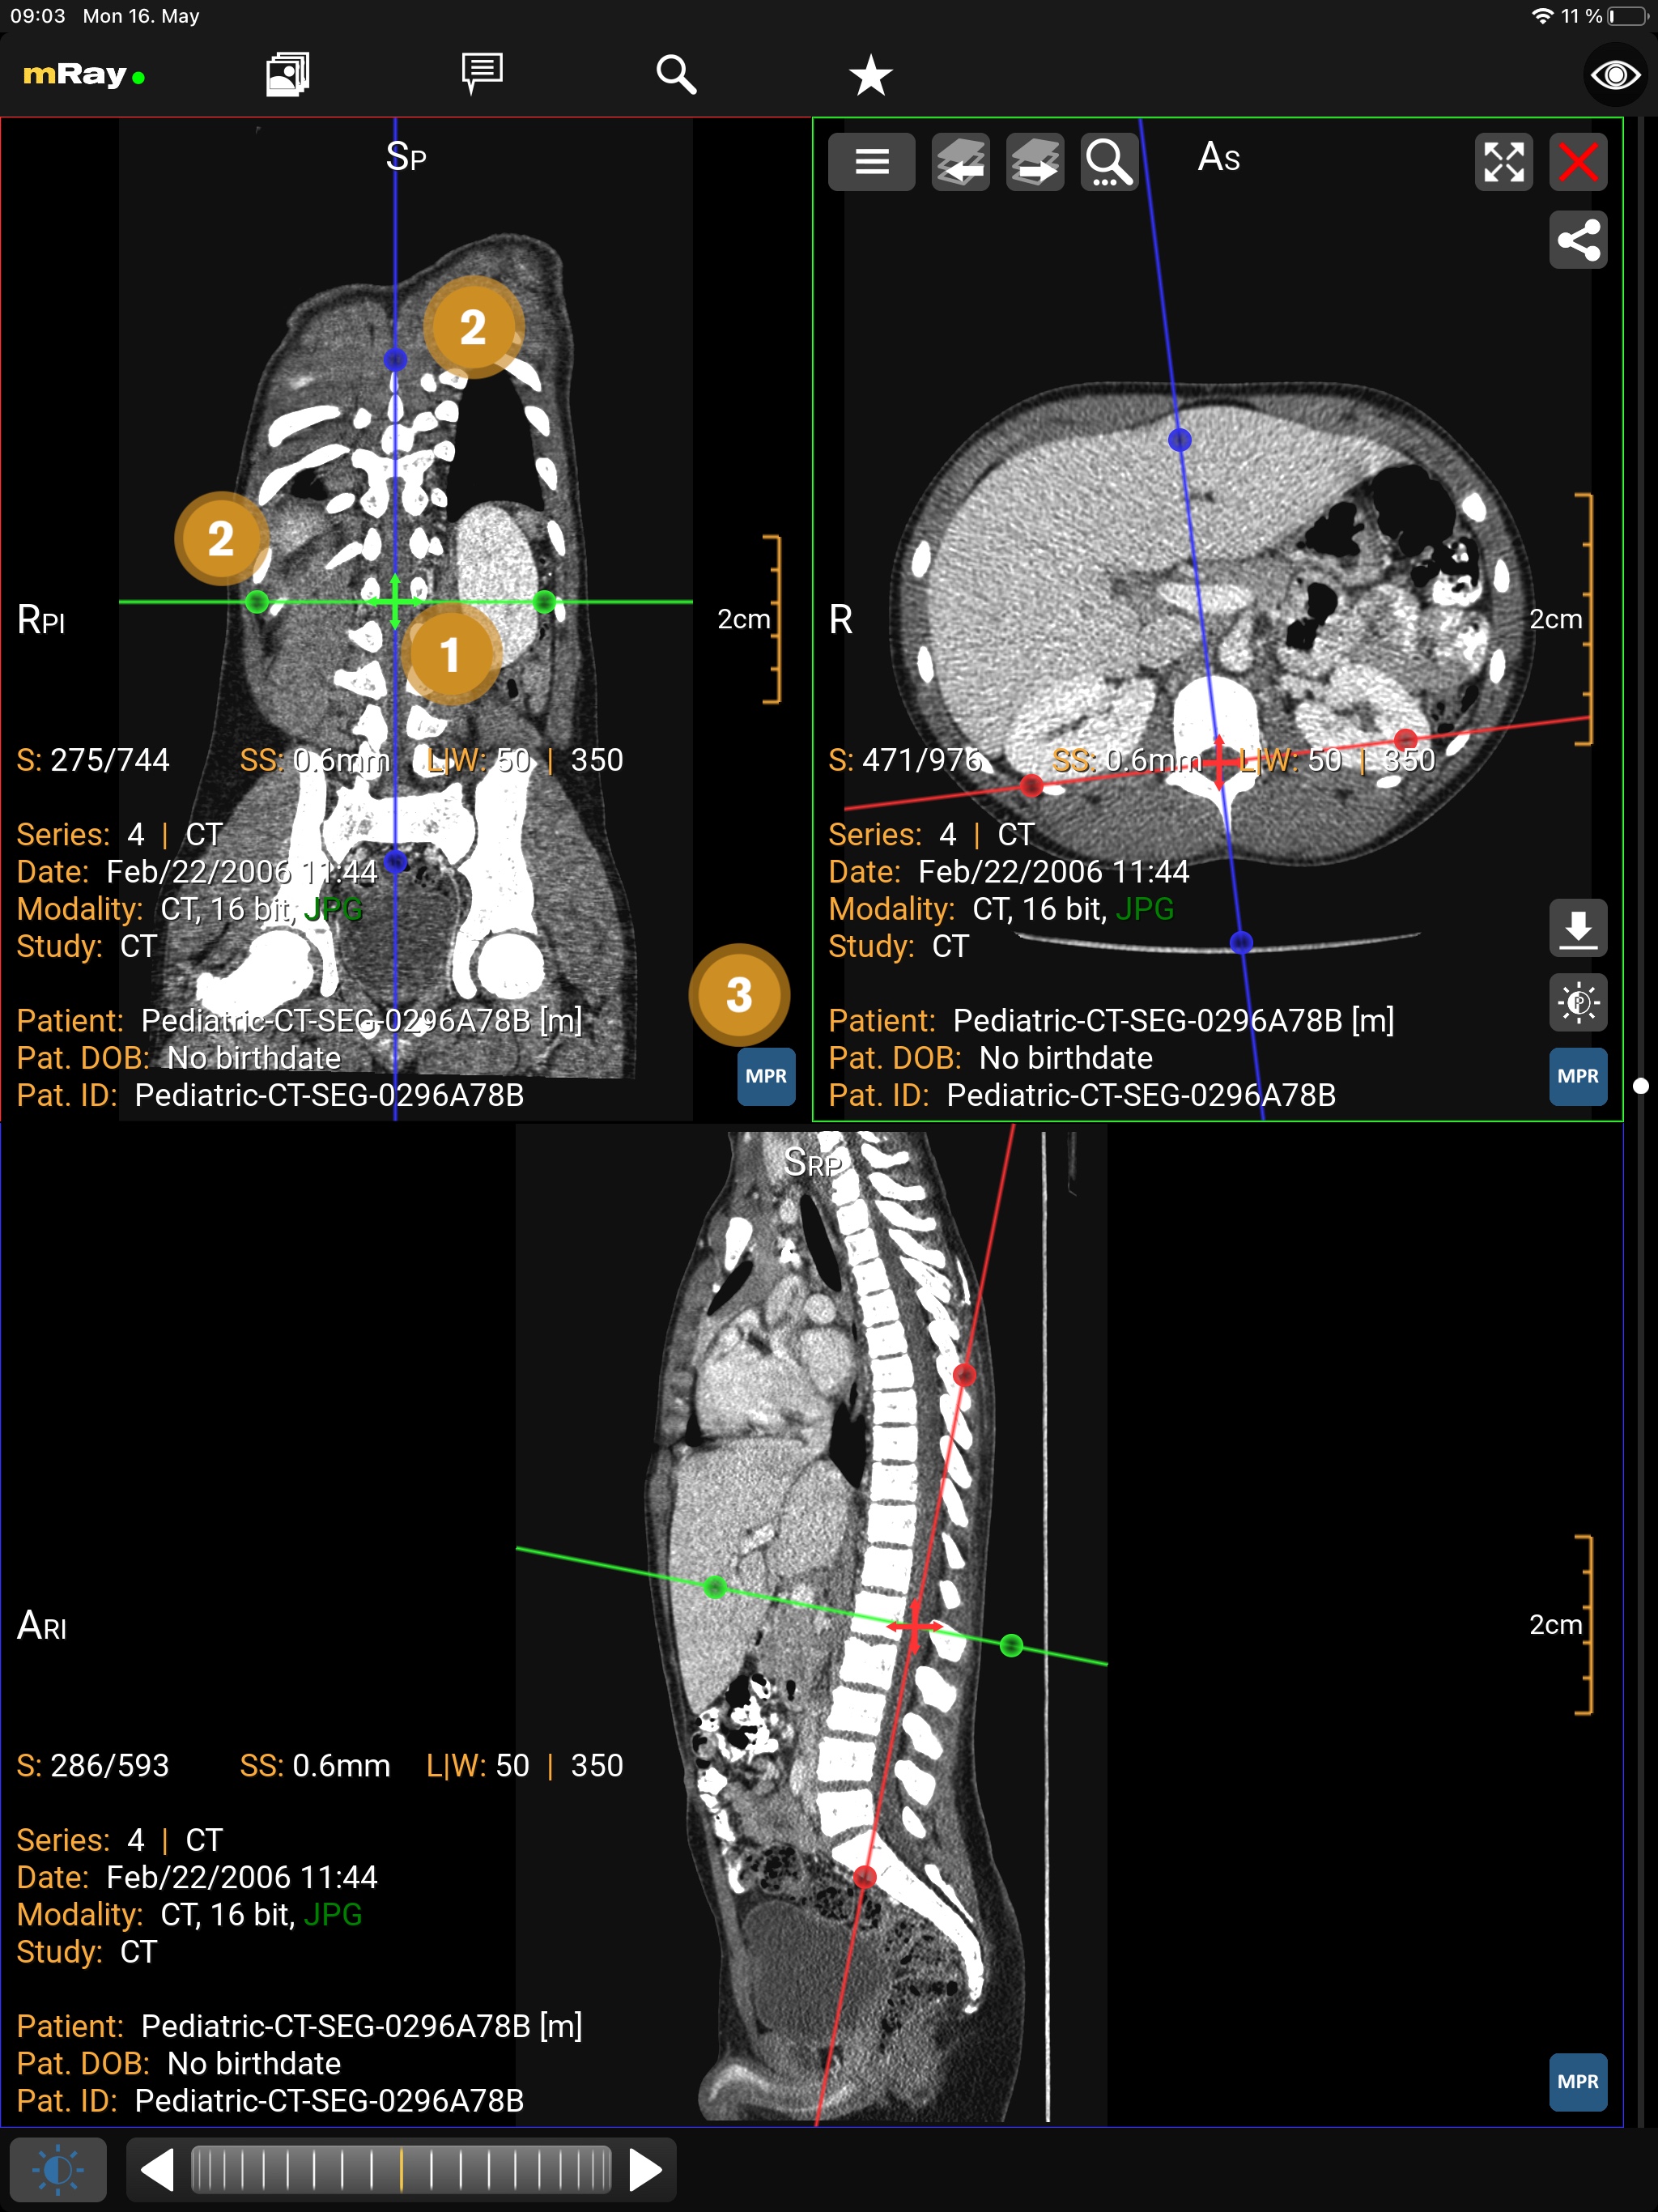

10.4. MPR-Ansichten

Die MPR-Bildlaufleiste erlaubt es Ihnen, mehrere Ansichten gleichzeitig zu öffnen (MPR-Ansichten). Der folgende Screenshot zeigt die MPR-Bildlaufleiste:

Der Screenshot zeigt die MPR-Bildlaufleiste eines MRTs von einem Fuß, die lokal berechnete Rekonstruktion (MPRs) und Informationen zum angezeigten Datensatz.

-

Der Split-Button

erlaubt es dem Nutzer weitere Fenster hinzuzufügen.

Die maximale Anzahl von Fenstern beträgt 2 bei Smartphones und 4 bei Tablets.

Vorübergehende Anzeige der Ansicht im Vollbildmodus und Rückkehr zum vorherigen Zustand mit den Maximieren

erlaubt es dem Nutzer weitere Fenster hinzuzufügen.

Die maximale Anzahl von Fenstern beträgt 2 bei Smartphones und 4 bei Tablets.

Vorübergehende Anzeige der Ansicht im Vollbildmodus und Rückkehr zum vorherigen Zustand mit den Maximieren  und Minimieren

und Minimieren  -Buttons.

-Buttons. -

Zeigt die aktuelle Ausrichtung der Ansicht in Bezug auf den originalen Datensatz. Button

, um die Ansichten zu wechseln.

, um die Ansichten zu wechseln. -

Der Verketten-Button

synchronisiert die Fenster.

synchronisiert die Fenster. -

Zeigt die Referenzlinien zu den jeweils anderen Fenstern.

Sie können die Perspektive mit dem "MPR-Perspektive"-Button (Punkt 2) verändern. Diese Funktion erlaubt es, zwischen Axial, Sagittal und Coronal zu wechseln. Der Button in der rechten unteren Ecke (Punkt 1) ermöglicht das Öffnen oder Schließen von weiteren Ansichten. Falls mehr als eine Ansicht geöffnet ist, erscheint ein Button um diese zu synchronisieren (siehe Synchronisierte Ansichten). Um mit der Ansicht interagieren zu können, müssen Sie entsprechende Ansicht zunächst auswählen. Dazu müssen Sie die Ansicht nur antippen. Die ausgewählte Ansicht wird dann hervorgehoben.

10.4.1. Beliebig orientierte MPR

Neben den orthogonalen Orientierungen Axial, Sagittal und Coronal können Sie die beliebig orientierte MPR im Werkzeugmenü aktivieren.

Der Screenshot zeigt den aktiven beliebig orientierte MPR Modus.

-

Verschieben der Schichtposition der anderen Ansichten.

-

Ändern der Orientierung der anderen Ansichten.

-

Zurücksetzen aller Ansichten zur orthogonalen Orientierung.

Um die Orientierung auf orthogonal zurückzusetzen, verwenden Sie die oben erwähnte MPR-Schaltfläche oder führen Sie einen Doppelklick aus. Durch wiederholtes Zurücksetzen können Sie die Reihenfolge der Ebenen innerhalb der Ansichten ändern. Sie können die MPR im Werkzeugmenü oder durch Schließen von Ansichten deaktivieren, bis nur noch eine einzige Ansicht übrig ist.